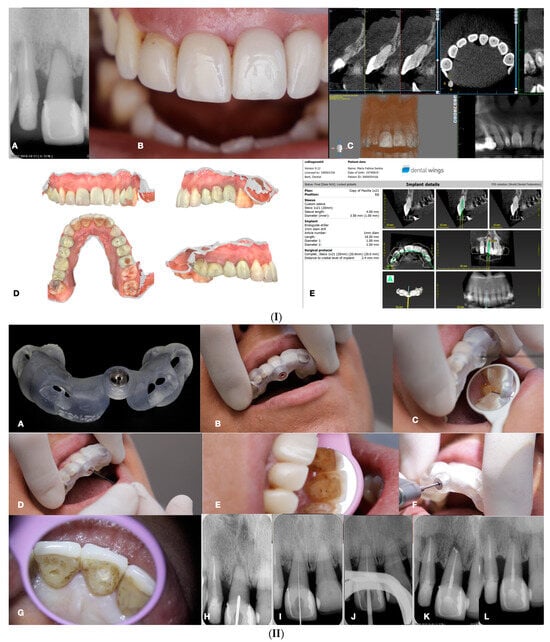

Figure 11.

(I) (A) Preoperative panorax focused on the impacted right maxillary canine, revealing a large lesion. (B) Two-year follow-up panorax after the surgical removal of the lesion revealing healing. (C,D) Periapical radiographs reveal recurrent disease 6 years after the surgical intervention. Notice that the maxillary canine was brought in occlusion with orthodontic treatment, but the canal was rendered radiographically blocked. (E,F) CBCT axial slices evaluate the magnitude of the periapical lesion and the root canal calcification of the maxillary canine. (II) (A,B) Clinical microscopic image from two different angles of the previously initiated access cavities. Notice the gray spot indicating the calcified root canal orifice (yellow arrow). (C) Clinical image of the initial troughing of the calcified canal with a round long shafted bur (Munce bur). (D) EDM file during the buckling resistance activation test negotiation technique. (E) Clinical image of the calcified orifice after the first BRAT stroke. Canal negotiation with the 08 D-finder file is now possible. (III) A Preoperative periapical radiograph. (B) Periapical radiograph demonstrating the initial negotiation of an 08 D-finder after the first BRAT stroke. (C) Periapical length determination radiograph. (D) Postoperative radiograph. (E) One-year follow-up periapical radiograph. (F–H) Three-year follow-up cbct reveals complete healing of the periapical lesion (axial slices) (clinical images and radiographs courtesy of Dr. Chaniotis Antonis). Red arrows indicate the calcified canal location, and Yellow arrows indicate the impacted canine. The white circle is the projection of a nose piercing ring in the radiograph (not a symbol).